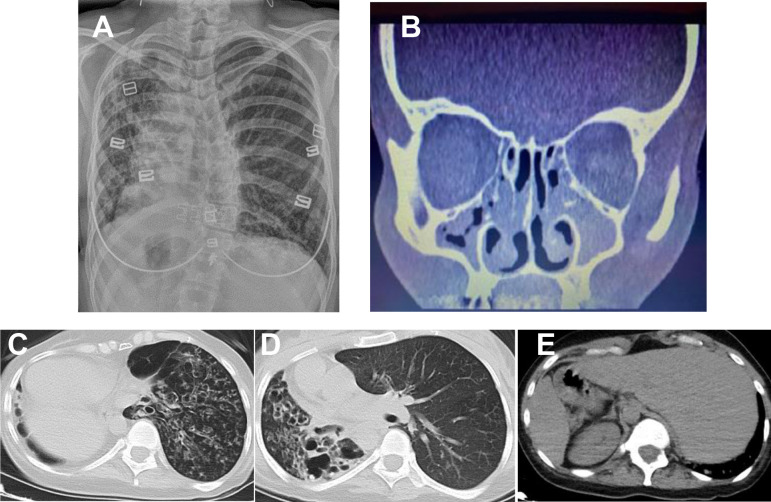

α-1抗胰蛋白酶缺乏症(AATD)是一种罕见的常染色体共显性疾病,由 SERPINA1 基因突变引起。最常与 AATD 相关的等位基因是蛋白酶抑制剂 S 和 Z。在此,我们报告了一名被诊断为 Kartagener 综合征的 35 岁女性,她随后被转诊进行支气管扩张检测。她被确认患有一种迄今未报道的 AATD 变异:SERPINA1 基因先前未定义的第 4 号外显子 (NM_001127701.1) 中的杂合变异 rs1460874866。虽然卡塔格纳综合征是支气管扩张症的遗传病因,但建议该综合征患者接受 AATD 检测。

Alpha-1 antitrypsin deficiency (AATD) is a rare autosomal co-dominant disease caused by mutations in the SERPINA1 gene. The alleles most frequently associated with AATD are protease inhibitors S and Z. Here, we report on a 35-year-old woman diagnosed with Kartagener's syndrome and subsequently referred for bronchiectasis testing. She was identified with a hitherto unreported AATD mutation: a heterozygous variant rs1460874866 in a previously undefined exon 4 (NM_001127701.1) of the SERPINA1 gene. Although Kartagener's syndrome is a genetic cause of bronchiectasis, patients with this syndrome are recommended to undergo AATD testing.